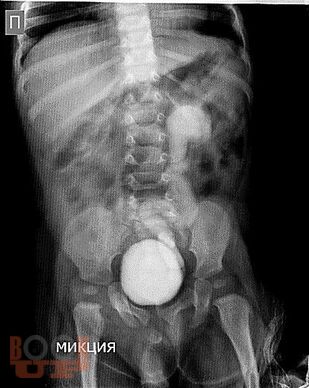

Учебное пособие предназначено для самоконтроля знаний студентов медицинских вузов, ординаторов и врачей детских хирургов, травматологов-ортопедов, детских урологов-андрологов и базируется на основных учебниках, европейских и российских клинических рекомендациях и учебных пособиях по детской хирургии. Используя его, можно в полной мере оценить усвоение студентами всего учебного материала и современных аспектов детской хирургии. Пособие содержит ситуационные задачи и ответы к ним, затрагивает все темы блоков модулей «Детская хирургия» и «Хирургические болезни у детей».